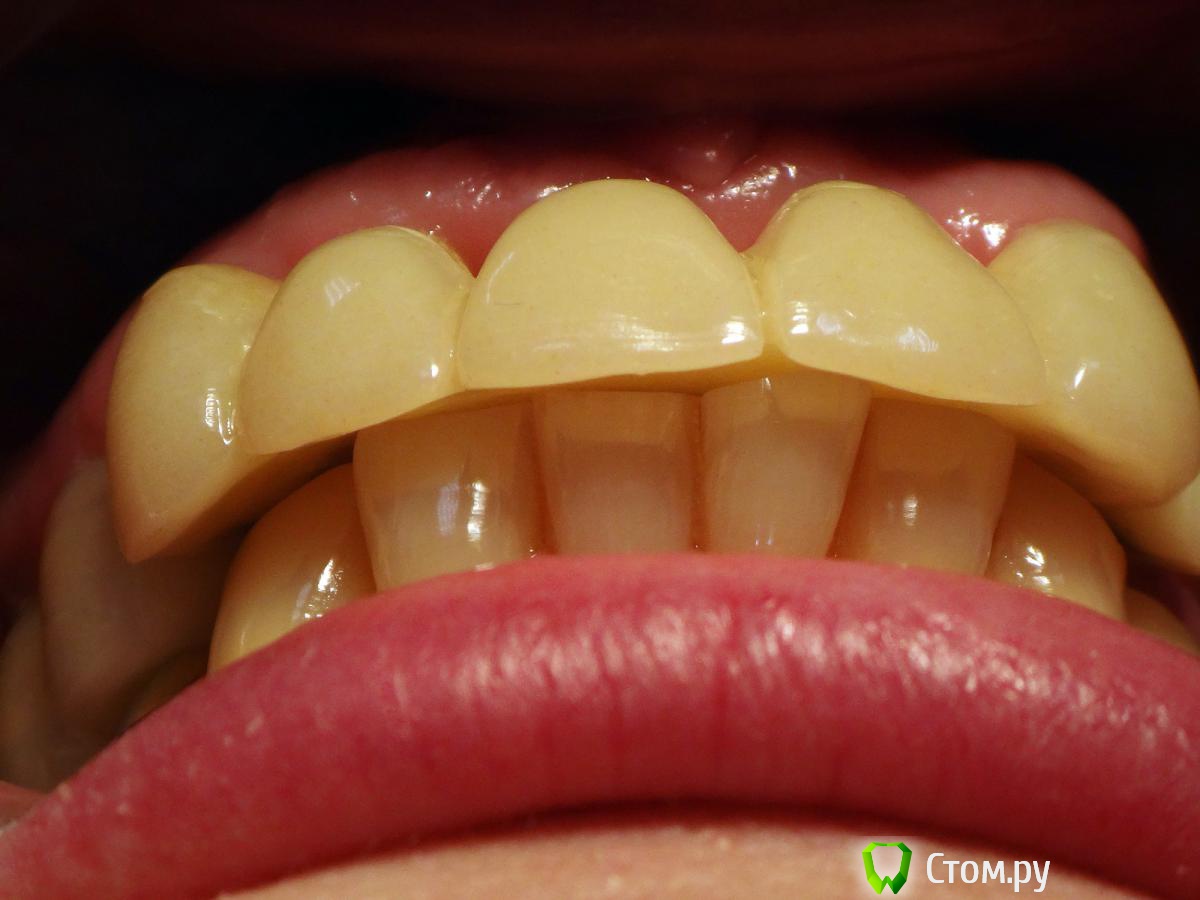

Kalipso Опубликовано 28 августа, 2014 Поделиться Опубликовано 28 августа, 2014 Я ставлю сразу после удаления .1 . Снимаю слепок до удаления , и прошу техника либо сделать коронку или wax up после чего по ключу сама изготавливаю .2. Удаляю .3.Жидкотекучим креплю коронку . Как- то так . Это наверно самая моя первая такая работа .http://s017.radikal.ru/i432/1408/7c/d61e22c1c7ae.jpg http://s018.radikal.ru/i519/1408/d2/23c0aebcd1b4.jpg http://s016.radikal.ru/i336/1408/51/3ede7c77a5d0.jpg http://s41.radikal.ru/i091/1408/cc/604419754cb7.jpg 3 Ссылка на комментарий

Kalipso Опубликовано 28 августа, 2014 Поделиться Опубликовано 28 августа, 2014 Спасибо за кейс. Сразу после удаления крепите или ждете какое-то время? Жидким крепите с протравливанием/бондом соседних зубов? Не возникает ли потом сложностей как снять это? Есть ли промывное пространство между десной и временной коронкой или клеете впритык?1.Удаление, гемостаз.2.бонд , коронка.3.все ок, иногда раньше времени слетает .4.не знаю правильно или нет но клею впритык . Проблем не было . 1 Ссылка на комментарий

Kalipso Опубликовано 5 сентября, 2014 Поделиться Опубликовано 5 сентября, 2014 Мне кажется или зениты у двоек будут разной высоты? Что делать если после удаления десна выше зенитов соседних? Получается если поставить времянку сразу же и ограничить десну , то овоид получится выше чем надо. Если подождать после удаления несколько дней, опустится ли десна?Именно в этом случае в дальнейшем планировалось хир. удлинение .Если вы хотите сохранить овойд делайте временную конструкцию одномоментно с удаление , если найду покажу фото где пациент пришел на третий день после вид совершенно другой . Ссылка на комментарий

Slaggy Опубликовано 11 сентября, 2014 Поделиться Опубликовано 11 сентября, 2014 (изменено) Если планируется удаление переднего зуба, то стараемся одномоментно установить имплантат. Если это невозможно или нельзя нагружать винт, то делаем адгезивный "мериленд". Если пролёт в несколько зубов, то только съёмное. Можно дополню?Если пролет в несколько зубов, но ограничивающие деффект зубы будут обтачиваться, то можно армировать времянки металлом.вторую фотку перезагружаю:Это как раз на 3-4 день овоиды сделаны. первая фотка на 3-4 день после 3-4 дня после удаления.Что скажите мне изменится в поверхностных слоях сгустка и окружающих их тканей за 3-7 дней? Прорастет чем? или что?Нифига не вижу разницы одномоментно или на 3 день. Ааа. Есть разница. Не кровит и можно работать.А еще пациент осознав потерю значимей оценит обретение. Если удаляемый зуб имеет коронку, то можно его использовать для времянки.Извините за качество, не успел отфоткать - фотик сдох, успел пару раз нажать на затвор без подготовки.Вся центральная группа с клиновидными деффектами и подвижна, 21 - выдвинут на 3,5 мм. пациент не хочет с ним расстоваться, держит губами, оберегает.Нужен был быстрый "ход конем", чтоб он на шею не сел. Я пообещал за час сделать лучше чем есть. Пальцами удалил 21, обрезал под овоид, ретроградно запломбировал жидкотекучим, им же залил клиновидный и приклеил, армировав стекловолоконной лентой.Говенная работа, но она позволит мне дальше человека вывести на нормальное лечение.Вообще данный товрисч очень тяжелый, там все под бульдозер, а потом...Еще рас сорри за жесть, но это жизнь, работа, будни ))))) Изменено 11 сентября, 2014 пользователем Slaggy Ссылка на комментарий